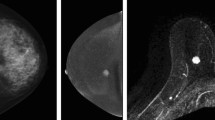

CESM (contrast-enhanced spectral mammography) is an efficient tool for detecting breast cancer because of its image characteristics. However, among most deep learning-based methods for breast cancer classification, few models can integrate both its multiview and multimodal features. To effectively utilize the image features of CESM and thus help physicians to improve the accuracy of diagnosis, we propose a multiview multimodal network (MVMM-Net).

The experiment is carried out to evaluate the in-house CESM images dataset taken from 95 patients aged 21–74 years with 760 images. The framework consists of three main stages: the input of the model, image feature extraction, and image classification. The first stage is to preprocess the CESM to utilize its multiview and multimodal features effectively. In the feature extraction stage, a deep learning-based network is used to extract CESM images features. The last stage is to integrate different features for classification using the MVMM-Net model.